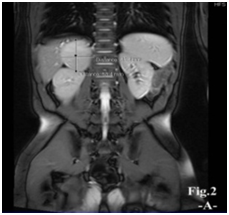

A 8.5- year-old boy presented with excessive pubic hair and other features of virilization for one year duration. On examination: he looks well, normal blood pressure, the height 121 cm (above 50th percentile), weight 30kg (75th percentile). Tanner stages for pubic hair, penile length (10cm) and testes volume (3 ml) were IV, IV, ІI respectively. No palpable abdominal mass, the rest of his physical examination unremarkable. Laboratory findings: FSH˂ 0.10 IU/L (1.4-15.4), LH 0.15 IU/L (1.2-7.8), testosterone 8 nmol/l (0.10- 1.04), 17 hydroxyprogesterone 2.1 ng/ml (0.2-3.5), cortical 346 mMol/L (168-728) ,Thyroid function tests, renal function tests and serum electrolytes were all normal. Imaging data: Bone age 11 years, abdominal ultrasonography showed well defined mass at right suprarenal region (49×48) mm., abdominal magnetic resonance demonstrated a mass at right suprarenal region measures (5×5)cm (Figure 1A) & (Figure 1B). Dynamic computed tomography of adrenal glands revealed: right adrenal mass (5×4x4)cm well defined associated with perilesional vessels, no invasion to surrounding structures. Brain magnetic resonance imaging was normal. Scrotal ultrasonography revealed both testes slightly enlarged in size with normal echogenesity chest X-ray normal. Based on the above data the interpretation was adrenal androgen-secreting tumor either adenoma or carcinoma. Therefore, the patient underwent right open adrenaloectomy: grossly; encapsulated mass, no invasion to surroundings, size (5×4x4). Histopathologic study was consistent with adrenocortical carcinoma confirmed by Immunohistochemistry (Figure 2 panel A) & (Figure 2 panel B). Postoperatively , on the first day, the patient complained of fatigue, and was found to have an undetectable morning serum cortisol level of ˂0.500 nmol/L (N: 171-536), Thus glucocorticoid replacement therapy was initiated, and he was scheduled for follow–up examination monthly for the first two years , scanning every 3 months for the first two years, 4 months for the next 2 years and every 6 months during the fifth year, since surgical treatment the patient has reported decreasing in features of virilization

Figure 2 Adrenal mass biopsy section stained with hematoxylinand eosin( panel A) shows  malignant tumor composed of solid sheets of atypical cells with dense compact eosinophillic cytoplasm, some cells have haveintranuclear inclusion, more than five mitosis per 50/HPF, capsular invasion, sinusodial invasion, focal clear cell component and broad fibrous bands.